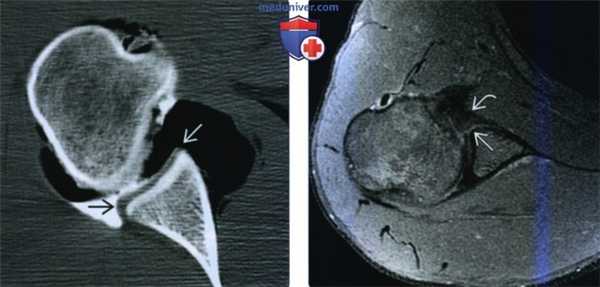

(Слева) Аксиальная Т1 FSМР-артрограмма: визуализируется костное повреждение Банкарта. Костные фрагменты сложно отличить от связочно-хрящевого комплекса на снимках с подавлением сигнала от жира и притупление переднего костного края В суставной впадины лопатки является важным ключом.

(Справа) Аксиальная КТ, этот же пациент, лучше визуализируется размер костного фрагмента. (Слева) Сагиттальная PD FS МР-артрограмма: определяется повреждение Банкарта. Суставная губа и небольшое костное кольцо отделены и смещены кпереди совместно с передним пучком нижней суставно-плечевой связки. Вогнутый контур передней костной части суставной впадины лопатки отражает небольшую утрату костной ткани.

(Справа) Сагиттальная 3D КТ с удаленной плечевой костью: визуализируется значительное костное повреждение Банкарта в, создающее картину «перевернутой груши». Процент утраты костной ткани исчисляется как отношение длины красной линии к зеленой, умноженное на сто. (Слева) Аксиальная Т1 FS МР-артрограмма: определяется разрыв через структуру суставной губы и небольшая паралабарная киста.

(Справа) Аксиальная КТ-артрограмма: визуализируется хроническое костное повреждение Банкарта с частичным заживлением, распространяющееся по диагонали поперек переднего угла суставной впадины. Подлежащий хрящ истончен.